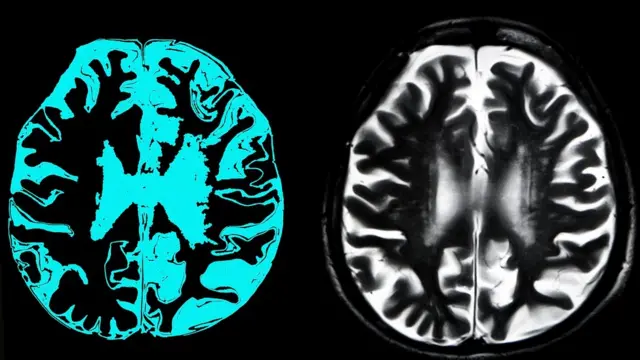

2019'da ölümle yaşam arasındaki çizgi muğlaklaştı.

Domuz beyinleri hayvanlar kesildikten dört saat sonra kısmen canlandırıldı.

Araştırma beyin hücrelerinin ölümlerinin ertelenebileceğini ve beyindeki bazı bağlantıların tekrardan canlandırılabildiğini gösterdi.

Bunun için domuzların kesilmiş kafalarının içine sentetik bir kan, kalp gibi ritmik bir şekilde pompalandı.

Kan pompalanınca beyin kısmen canlandı. Fakat beyinde bilinç veya farkındalığa dair bir sinyal olmadı.

Bu sürpriz bulgu, beynin kan gitmemesinden dakikalar sonra geri döndürülemez hasara uğradığı fikrini sarsabilir ve beyin hasarlarına yönelik yeni tedavi yöntemlerinin kapısını aralayabilir.